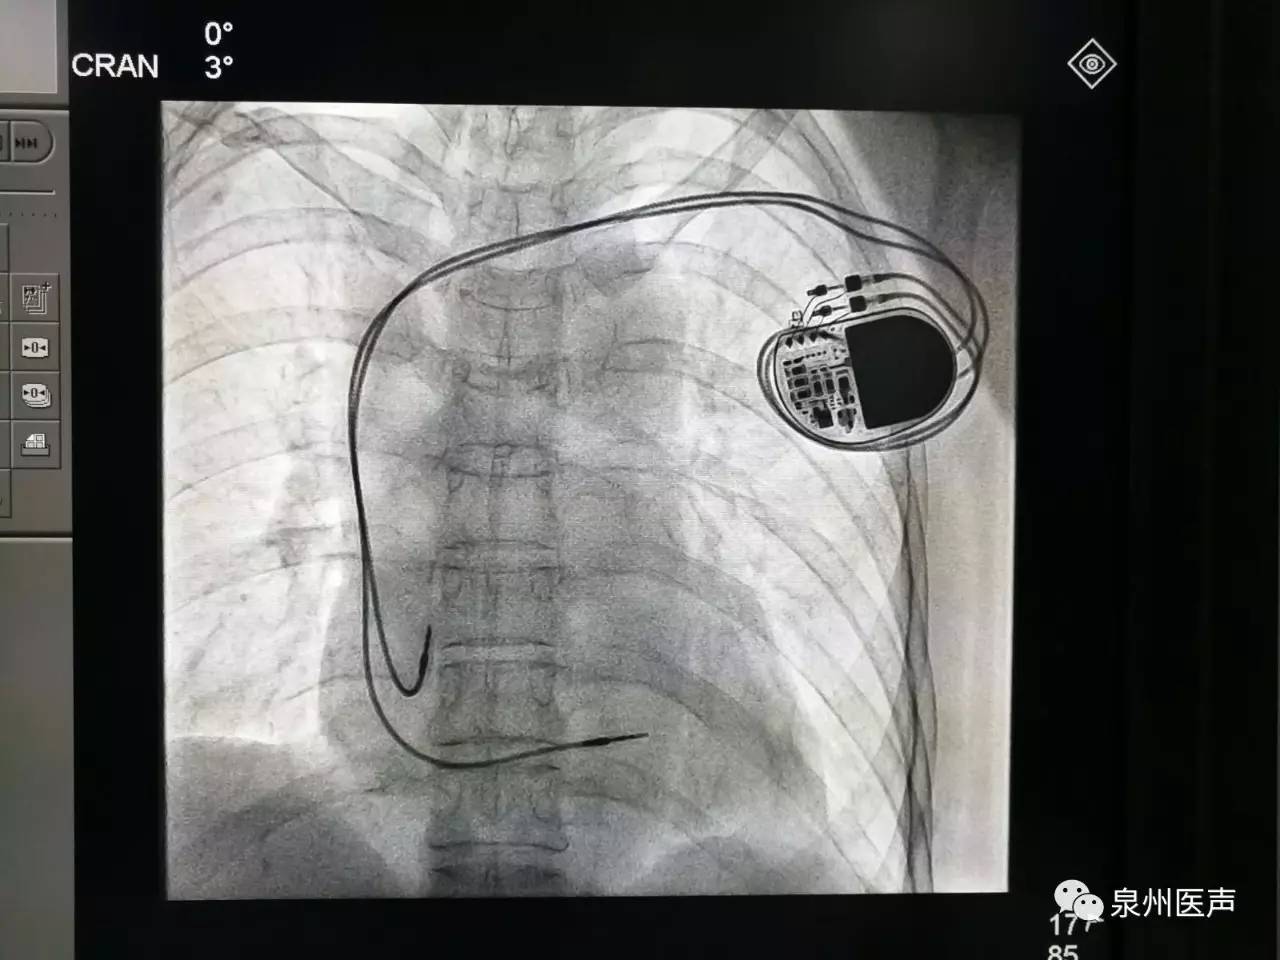

微創(chuàng)、樂普、先健填補(bǔ)國產(chǎn)起搏器市場空白,釋放哪些信號(hào)?

世界最小起搏器,正式進(jìn)入中國市場!

最高級別!美敦力緊急召回1.3萬個(gè)雙腔植入式心臟起搏器!

心臟起搏器的日常護(hù)理